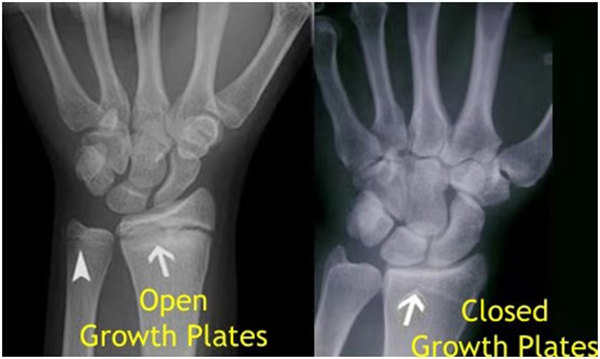

其實想要了解孩子的生長發(fā)育情況或者說孩子未來身高的趨勢,測骨齡是個好辦法。臨床上通常拍攝兒童的左手正位X光片 , 采用《中華-05》骨齡標準對手腕骨發(fā)育程度進行骨齡評價。